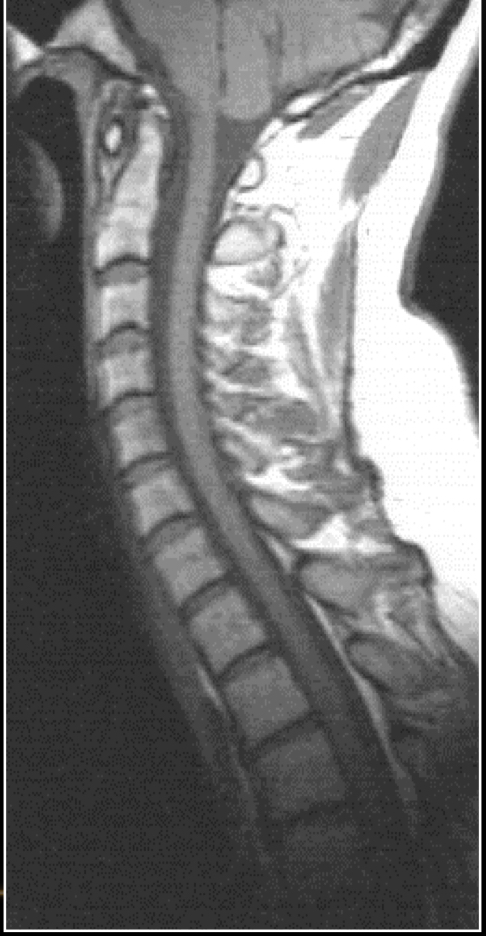

Is this a T1 or T2 weighted MRI? Why?

T1 wieghted because fluid filled cavities (CSF of spinal column, IVDs) are dark grey